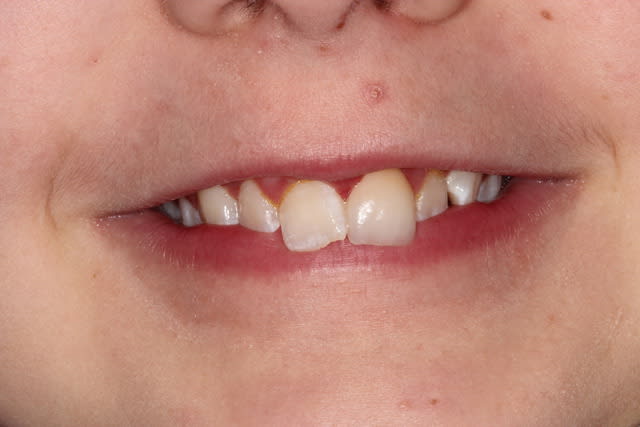

Petit patient de 9 ans vu il y a un an et demi. Patient hyperactif, un peu casse cou. Fracture enamelodentinaire sur 21.

Réparation au composite qui s'est cassée la figure au bout de quelques semaines. Je l'ai refaite, mais rebelote. Au bout de plusieurs echecs du composite j'ai décidé de tenter une facette céramique malgré :

- l'absence de maturité parodontale

- l'odf à faire

- l'hygiene moyenne

- et c'était seulement mon deuxieme cas de facette dans ma jeune carriere...

Bref, je l'ai revu ce matin, un an aprés la pose de la facette. Ca a tenu (heureusement...) et c'est pas trop vilain, même si on peut critiquer les caractérisations de la ceramique.

Initial cqk4j5 - Eugenol

1an lluriz - Eugenol

Preparation mirsy2 - Eugenol

1anbis w2qfux - Eugenol